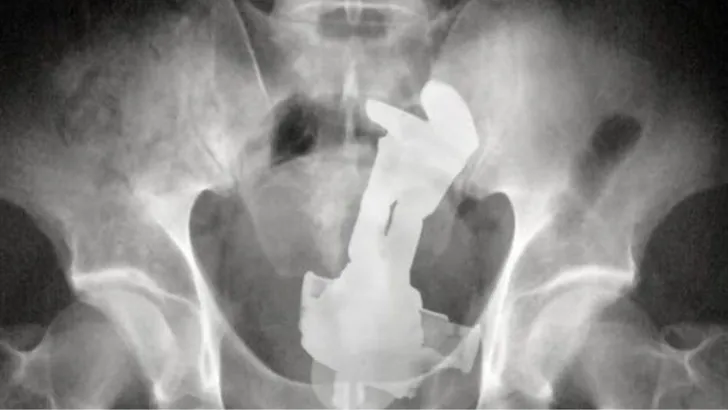

Natuurlijk staan de meeste mensen met een bizarre maag- of darminhoud niet te springen om met naam en toenaam in het nieuws te komen. Zeker niet omdat de vreemde inhoud in de endeldarm of vagina vaak gevolg is van vreemde seksspelletjes. Zoals de vrouw van wie doktoren alleen de röntgenfoto publiekelijk maakten. Bij haar werd een vibrator in haar darmen gevonden. Raar, maar daar we kunnen ons – met enige tegenzin – nog wel iets bij voorstellen. Wat de foto zo bijzonder maakt zijn de twee slavorken die erbij werden aangetroffen. Kennelijk had iemand in haar omgeving gedacht: geen zorg, ik haal die vibrator er wel even uit met deze vorken.

Vibrator en twee slavorken